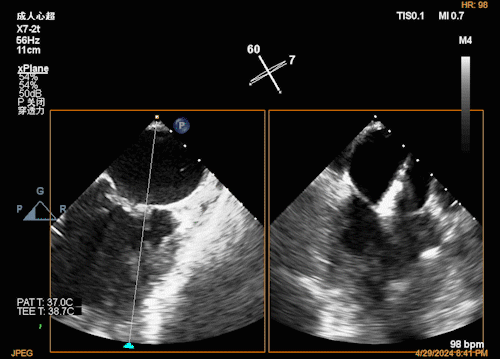

团队在反流最严重的2区精准植入1枚二尖瓣夹,即刻反流下降至微量,血压即刻上升20mmHg,跨瓣压差不升反降,由3mmHg降至2mmHg,改善效果明显,手术仅耗时一个半小时。 这是时隔四年继2020年指导开展区域内首例TAVR(经导管主动脉瓣置换)手术之后,陈茂教授再次带领华西团队,指导开展内自同城区域首例TEER术。陈茂教授对四院心内科心超图像的采集、房间隔穿刺的技巧、手术流程细节的把握、团队的默契配合、术前术后的管理表示称赞,鼓励四院心内科再接再厉造福区域患者。 患者为71岁老年女性,反复出现心累、气促已经超过10年,10多年来心衰的症状逐渐加重,间隔时间越来越短,且近1个月来已经3次因心衰住院,本次住院前已经无法耐受缓慢步行、如厕等日常生活,BNP超过了3000ng/ml。心电图为房颤,心超示左心室明显增大(65mm),重度二尖瓣反流(4+,CarpentierI+IIIb型),射血分数仅为31%。前叶长度:2.27cm且瓣尖增厚,后叶长度:1.14cm且局部钙化,瓣口面积:4.08cm2,反流宽度:1.7cm。患者及家属均拒绝外科开胸手术。 难点: 1.食道超声下该患者房间隔较厚较韧,且粗测高度仅为4.0cm,对穿刺的位置和技巧有较高要求; 2.左心扩大,反流宽度约17mm,放一个夹子可能不能有效解决反流,如放两个夹子需side by side 平行放置,但放置两个夹子有术后狭窄的风险; 3.前后叶对合似有间隙,若选用长宽夹子,会增加瓣叶张力,有瓣叶撕裂的风险,若选用短宽夹子,其捕获瓣叶的难度将增加; 4.患者心功能极差,手术需稳、准、快,不能耐受任何并发症风险。 影像资料 房间隔穿刺

![]() ![]() 瓣上瓣膜夹位置调整